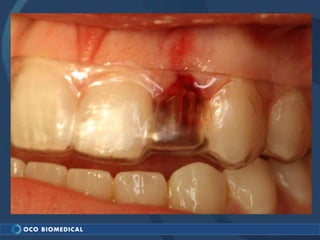

A 3.0mm dental implant was placed to replace congenitally missing maxillary lateral incisors. Dr. Tim Kosinski used a 1.8mm pilot bur and tissue punch to prepare the osteotomy site, then placed the implant by hand and seated it with a torque wrench. After ensuring the implant trajectory was within the restorative envelope, an acrylic coping was placed for temporary fabrication. At the 1 week post-op appointment, excellent soft tissue response and papilla formation were observed, and a final impression was taken to send to the lab for crown fabrication.